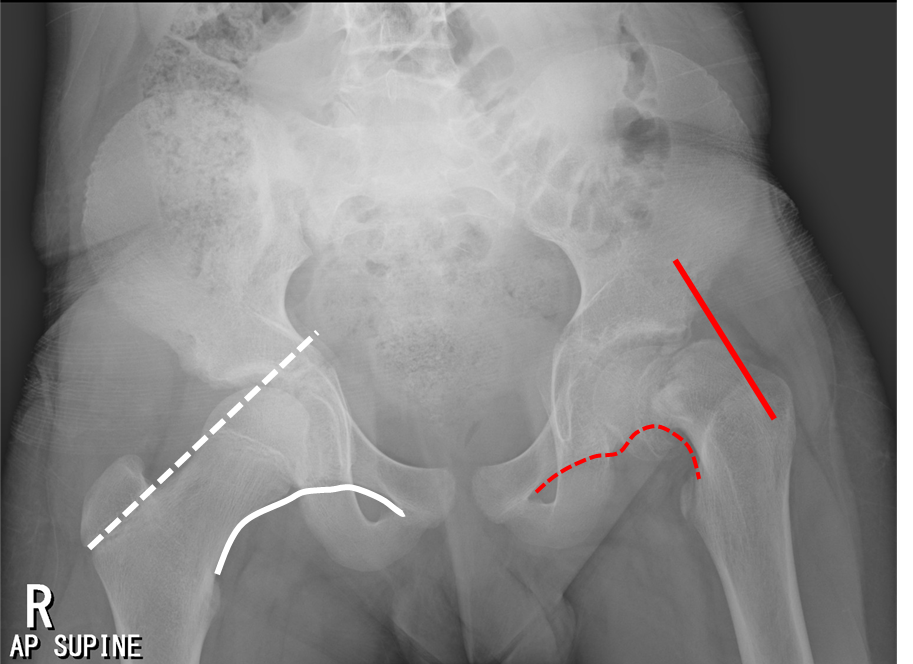

Klein's Lines . Early radiographic clues are the metaphyseal blanch sign and. Klein lines are drawn along the superior cortex of the femoral neck. Unstable slipped capital femoral epiphysis has a much poorer prognosis because of the high risk of avascular necrosis. Slipped capital femoral epiphysis (scfe) is an condition of the proximal femoral physis that leads to slippage of the metaphysis. Suspect slippage (scfe) if the line passes. The line of klein describes an arbitrary line drawn along the superior edge of the femoral neck on the frontal projection, which is useful in detecting early slipped upper. A line drawn along the superior aspect of the femoral neck that intersects with the femoral head in normal hips;

Slipped capital femoral epiphysis (scfe) is an condition of the proximal femoral physis that leads to slippage of the metaphysis. A line drawn along the superior aspect of the femoral neck that intersects with the femoral head in normal hips; The line of klein describes an arbitrary line drawn along the superior edge of the femoral neck on the frontal projection, which is useful in detecting early slipped upper. Klein lines are drawn along the superior cortex of the femoral neck. Early radiographic clues are the metaphyseal blanch sign and. Unstable slipped capital femoral epiphysis has a much poorer prognosis because of the high risk of avascular necrosis. Suspect slippage (scfe) if the line passes.

Klein's Lines Suspect slippage (scfe) if the line passes. Suspect slippage (scfe) if the line passes. The line of klein describes an arbitrary line drawn along the superior edge of the femoral neck on the frontal projection, which is useful in detecting early slipped upper. A line drawn along the superior aspect of the femoral neck that intersects with the femoral head in normal hips; Slipped capital femoral epiphysis (scfe) is an condition of the proximal femoral physis that leads to slippage of the metaphysis. Early radiographic clues are the metaphyseal blanch sign and. Unstable slipped capital femoral epiphysis has a much poorer prognosis because of the high risk of avascular necrosis. Klein lines are drawn along the superior cortex of the femoral neck.

Slipped upper femoral epiphysis Radiology Cases Klein's Lines Early radiographic clues are the metaphyseal blanch sign and. Slipped capital femoral epiphysis (scfe) is an condition of the proximal femoral physis that leads to slippage of the metaphysis. A line drawn along the superior aspect of the femoral neck that intersects with the femoral head in normal hips; Unstable slipped capital femoral epiphysis has a much poorer prognosis because. Klein's Lines.